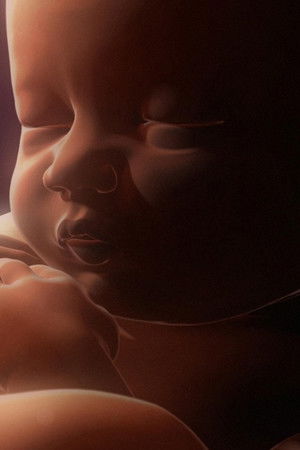

Advanced technology, groundbreaking scientific discoveries about the beginnings of life, and computer animation all combine to detail how multiple siblings develop in the womb as the filmmakers at National Geographic explore the fetal growth of twins, triplets, and quadruplets. Detailed pictures of these different groupings in various stages of fetal development bring the earliest stages of life to the screen as never before.